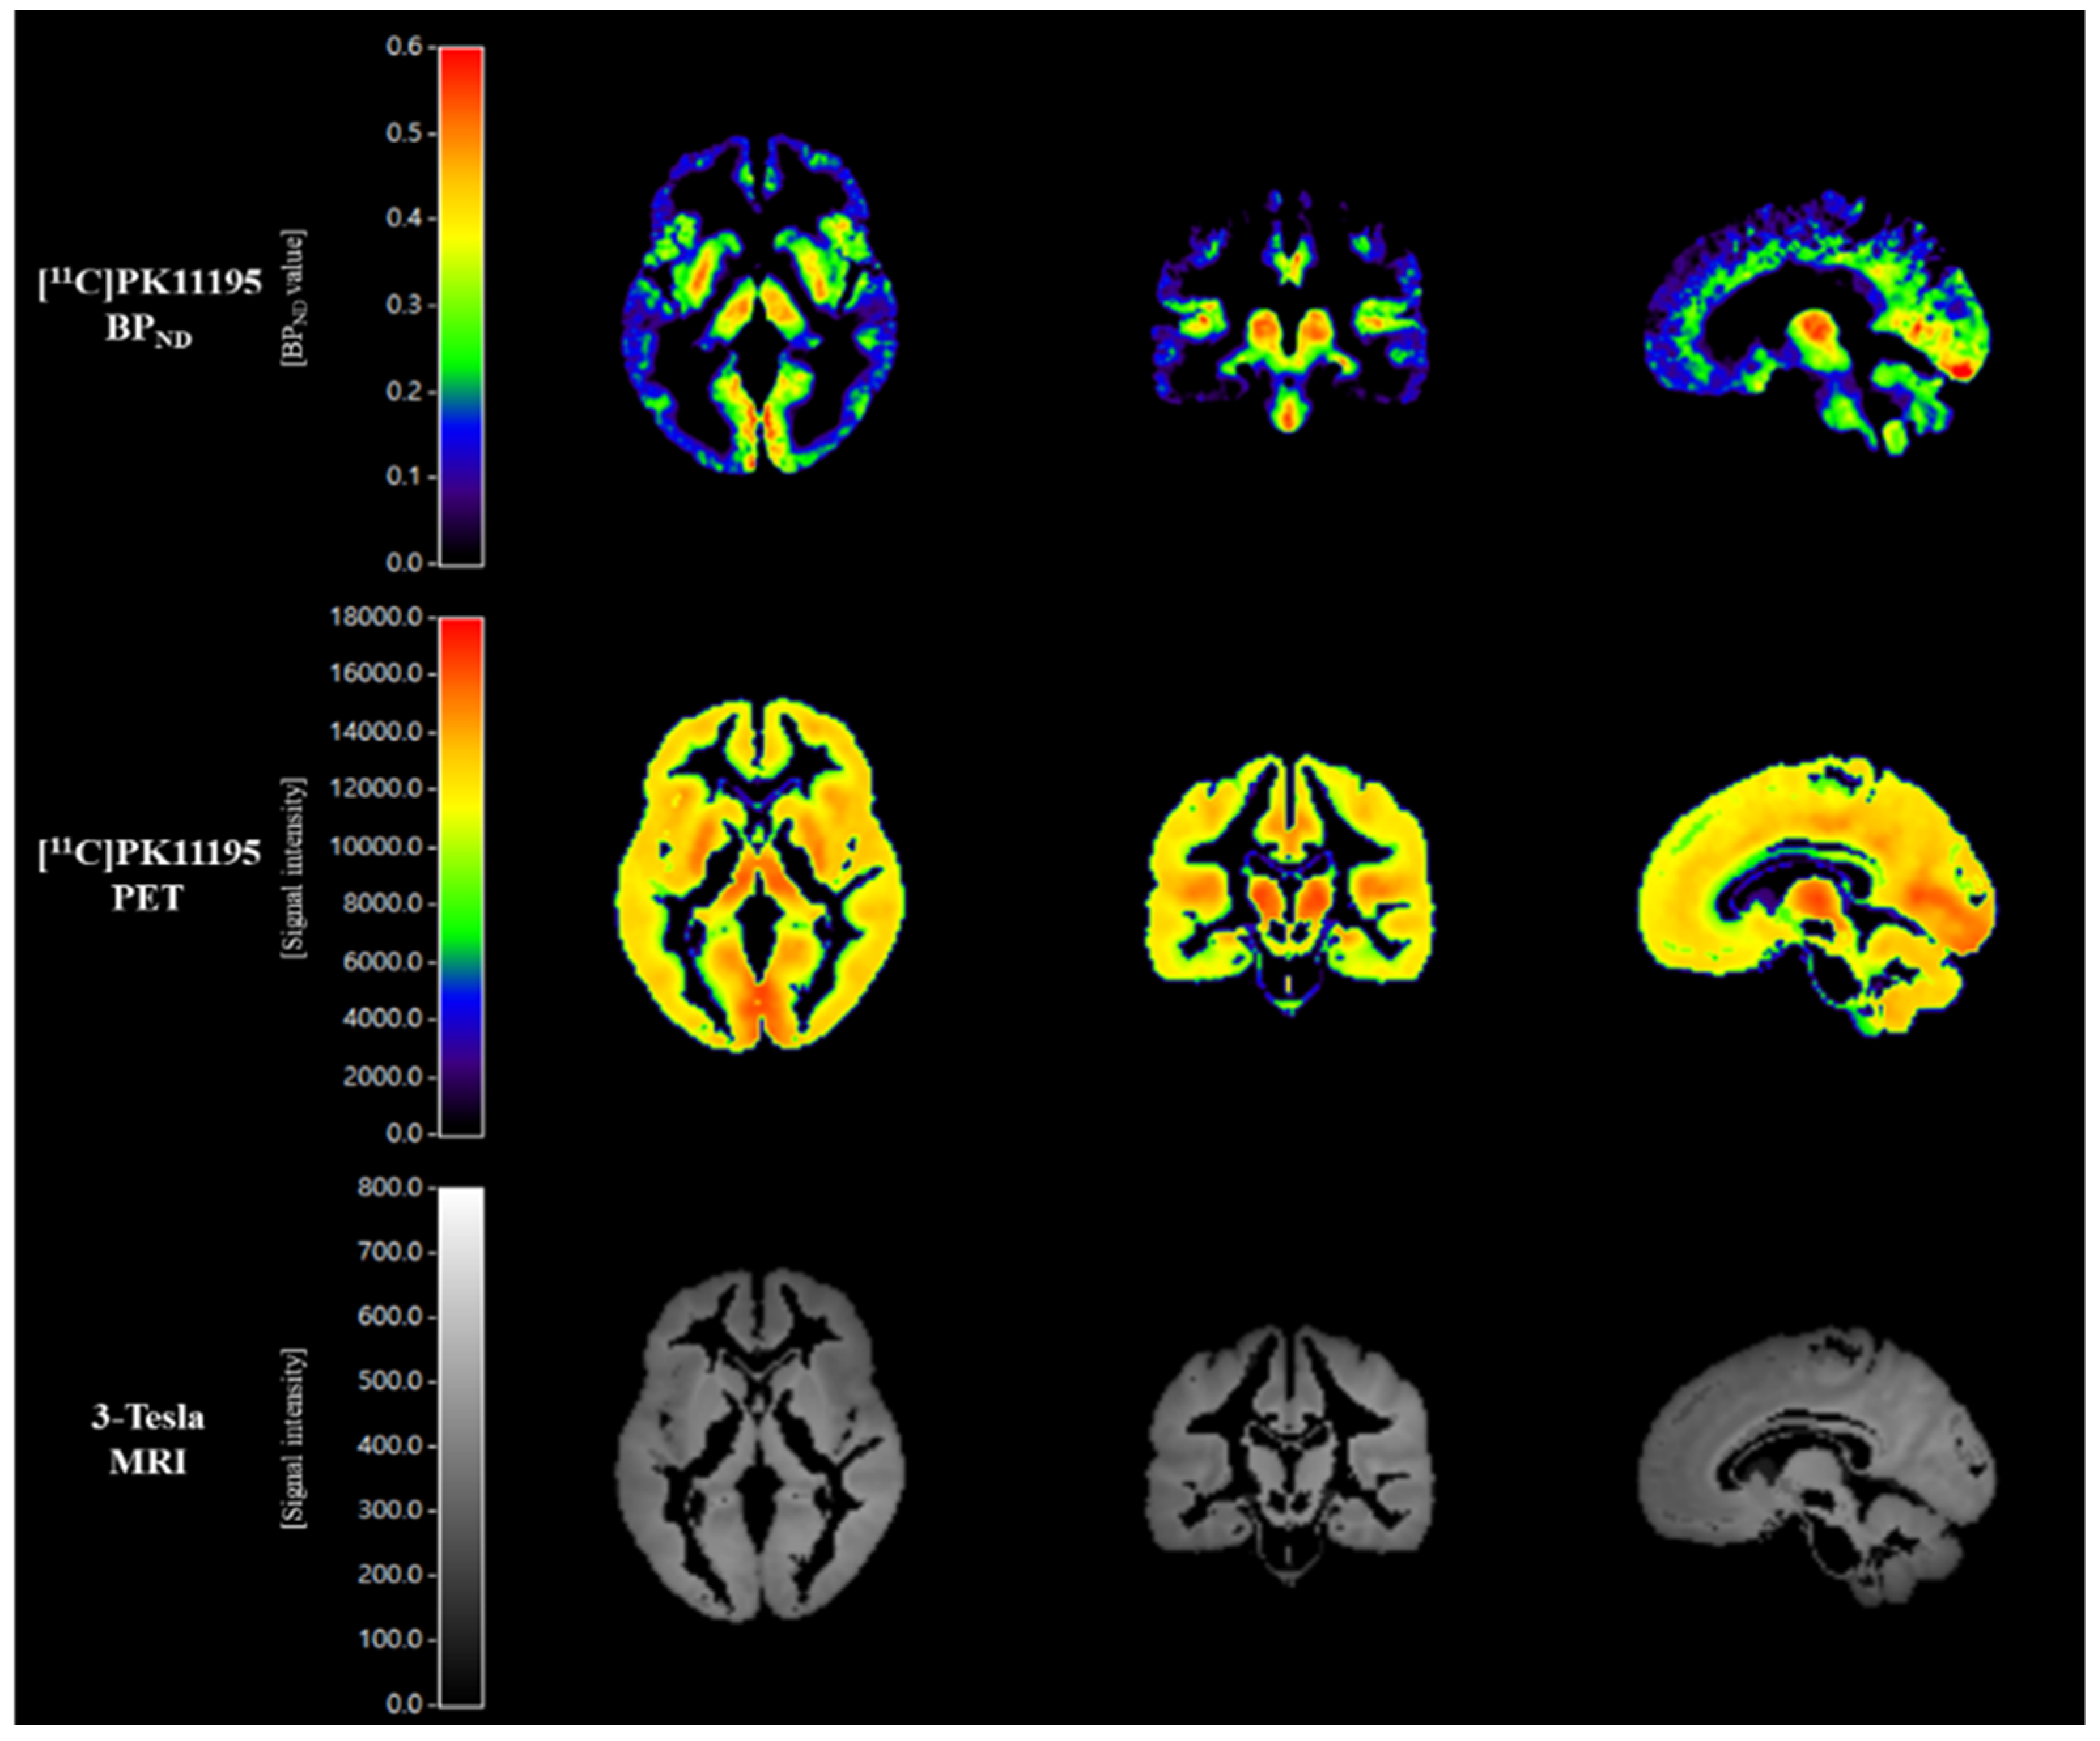

2.3. Scanning Protocol for [11C]PK11195 PET Imaging

2.4. [11C]PK11195 PET Imaging Analysis